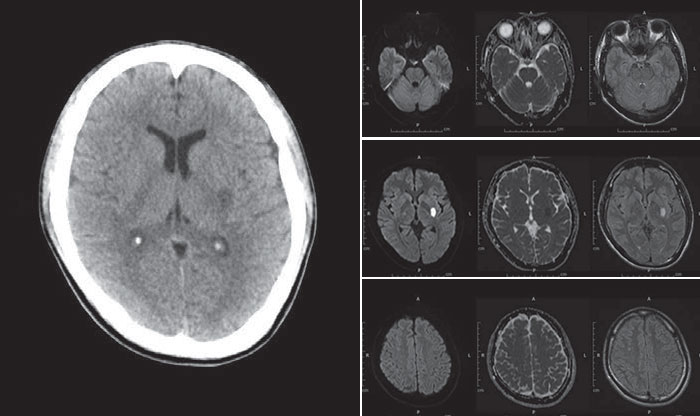

QUESTION NO.50